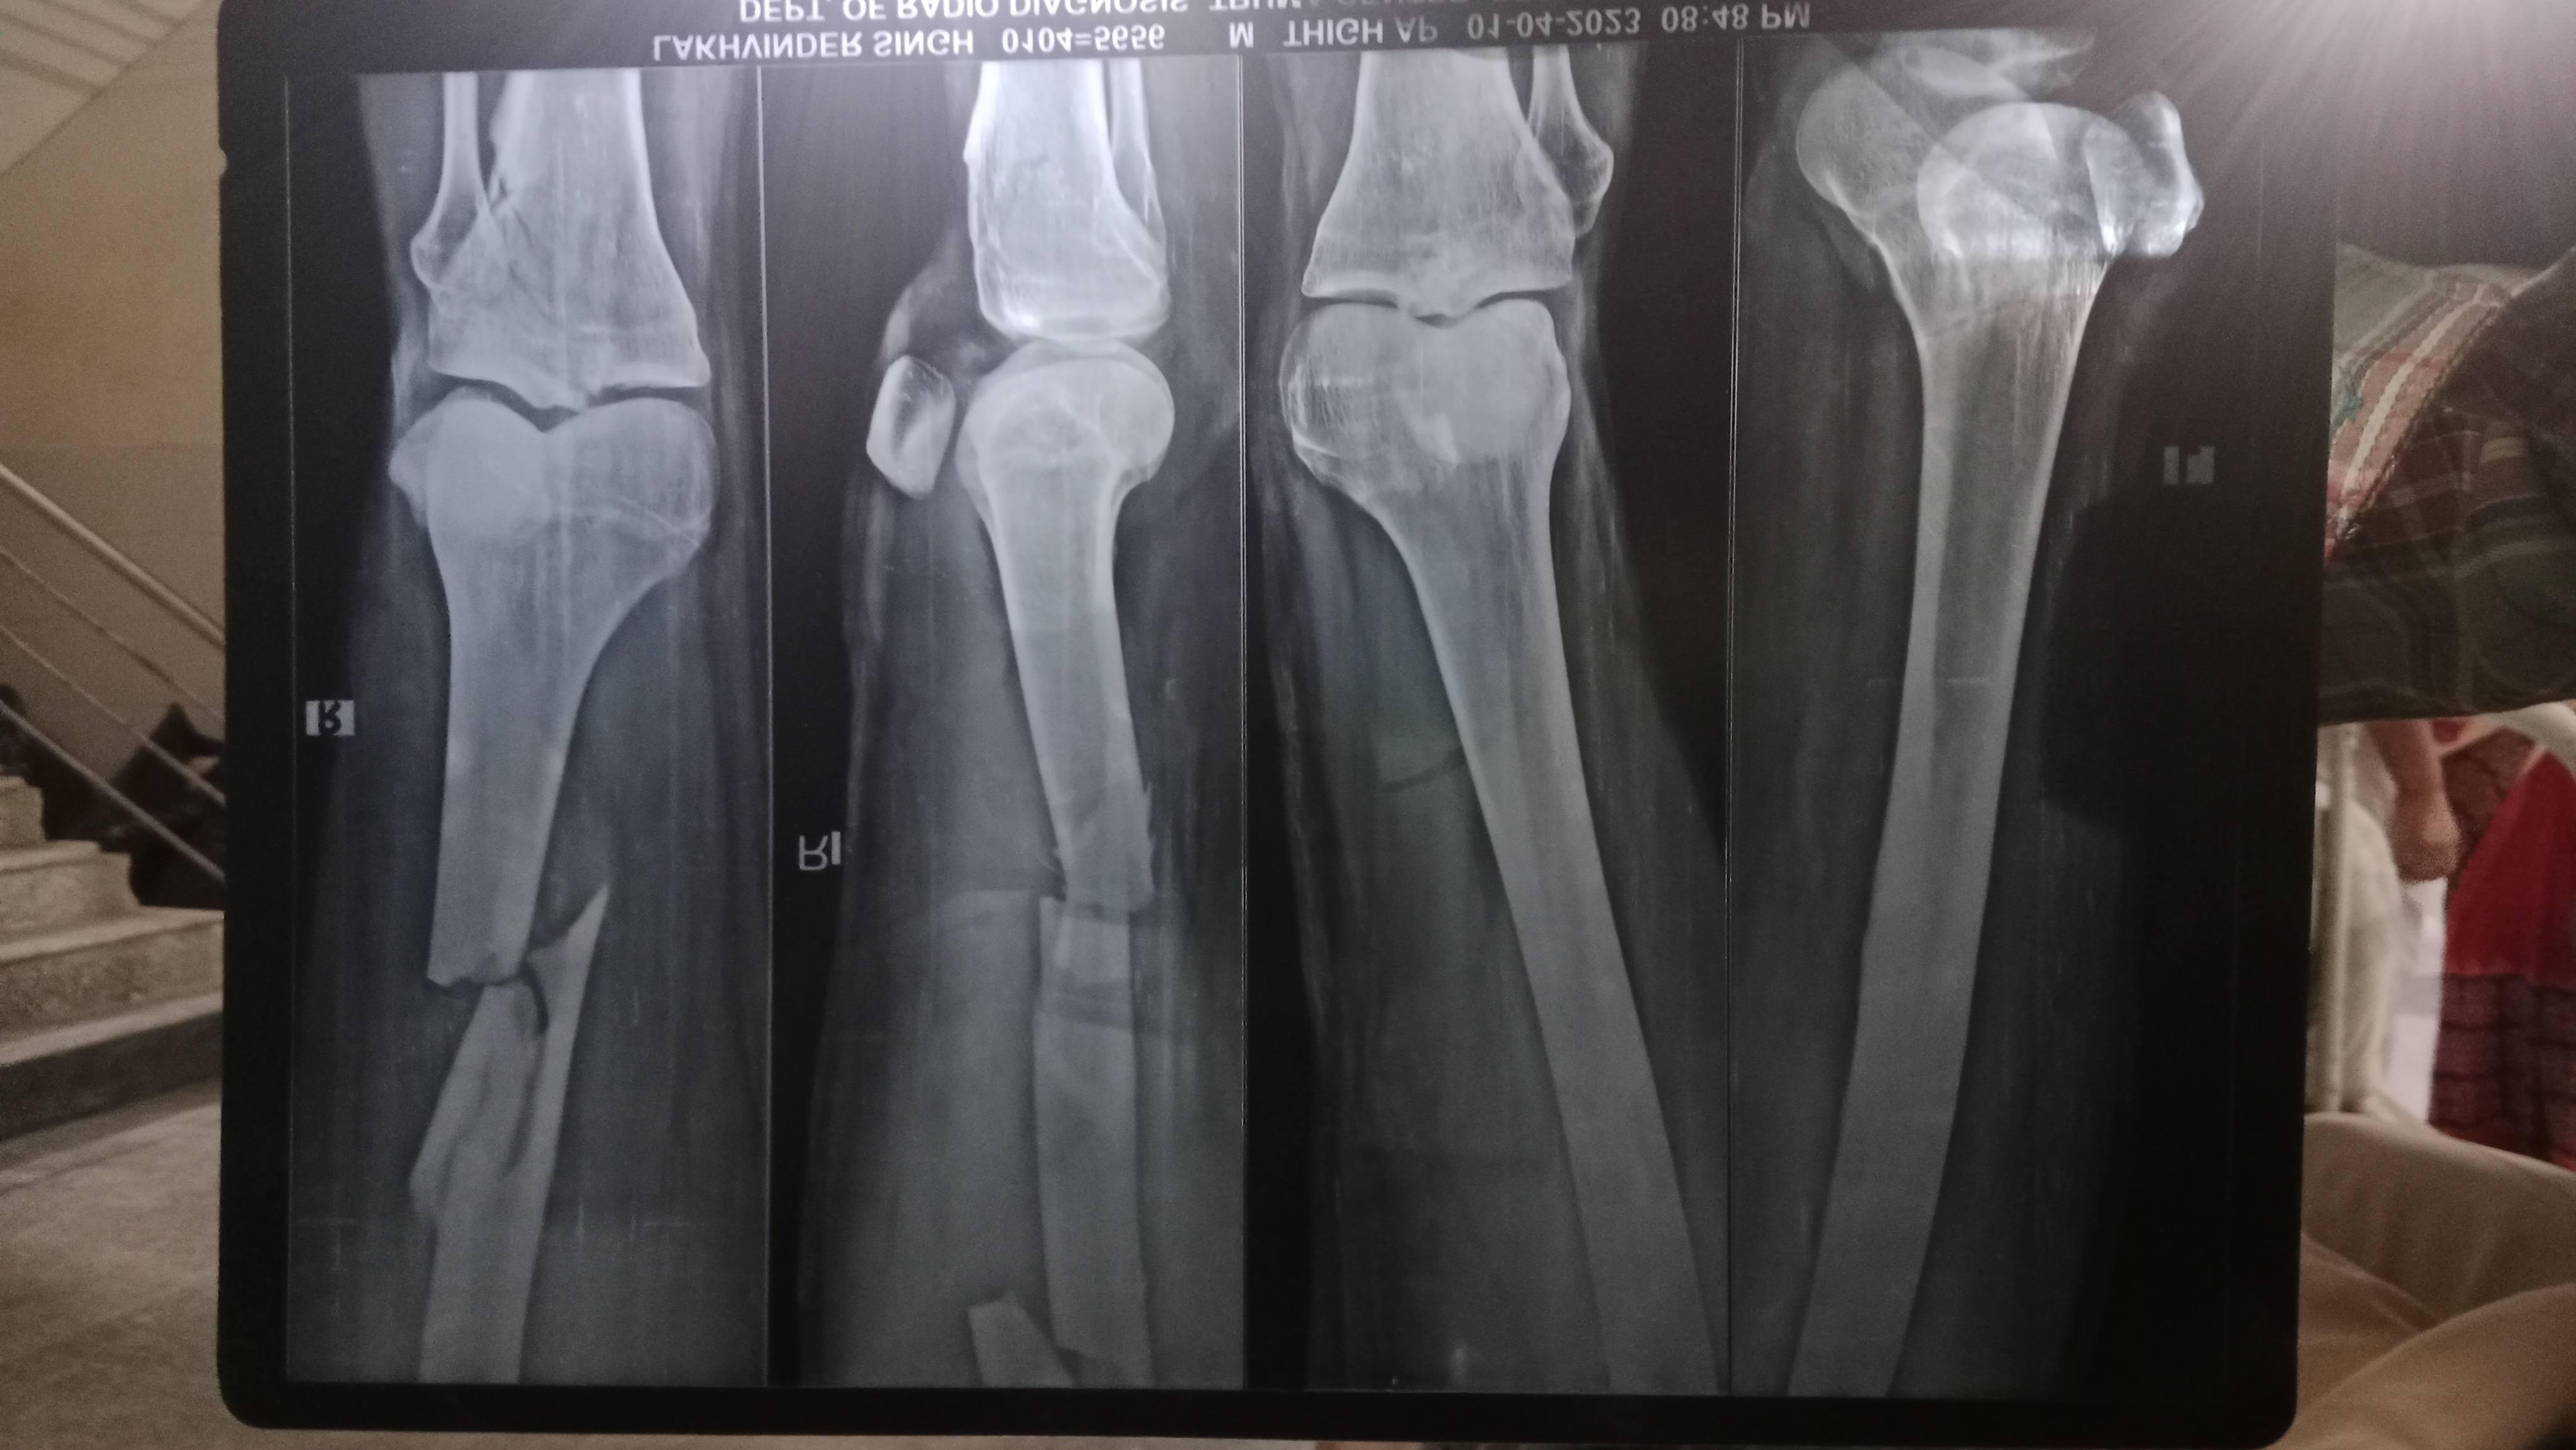

X_ Ray hai clavicle bone ka